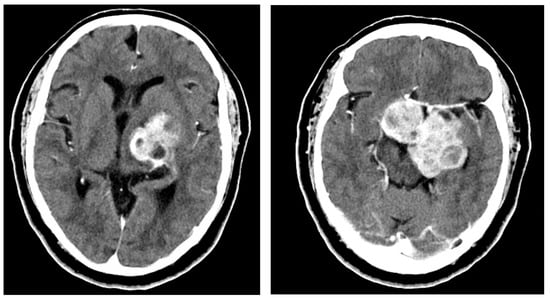

2.1. Case 1

2.2. Case 2